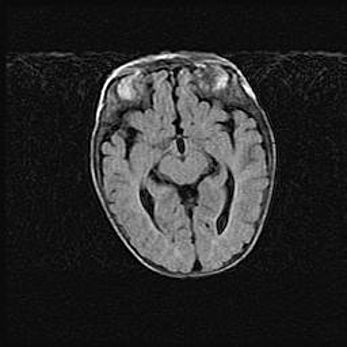

Наружная гидроцефалия с возможной атрофией височных областей.

Возраст: 28 дней

Вес: 3670 г

Пол: мужской

Окружность головы: 38 см

Срок гестации: 40 недель

Гидроцефалия головного мозга у новорожденных – это заболевание, которое характеризуется скоплением избыточного количества спинномозговой жидкости в желудочковой системе головного мозга в результате затруднения её перемещения от места выработки к месту поглощения в кровеносную систему или вследствие нарушения абсорбции. При открытой наружной форме гидроцефалии у новорожденных расширяются и переполняются субарахноидные пространства.

При нормотензивных  формах,  которые,  как  правило,  являются  следствием  перенесенных ишемических  повреждений  паренхимы  мозга,  возможно  сочетание микроцефалии  с нормотензивной гидроцефалией. В основе данных изменений лежит атрофия больших полушарий с преимущественной  локализацией  в  лобно-височных  областях.